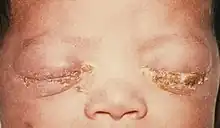

| A newborn with gonococcal ophthalmia neonatorum | |